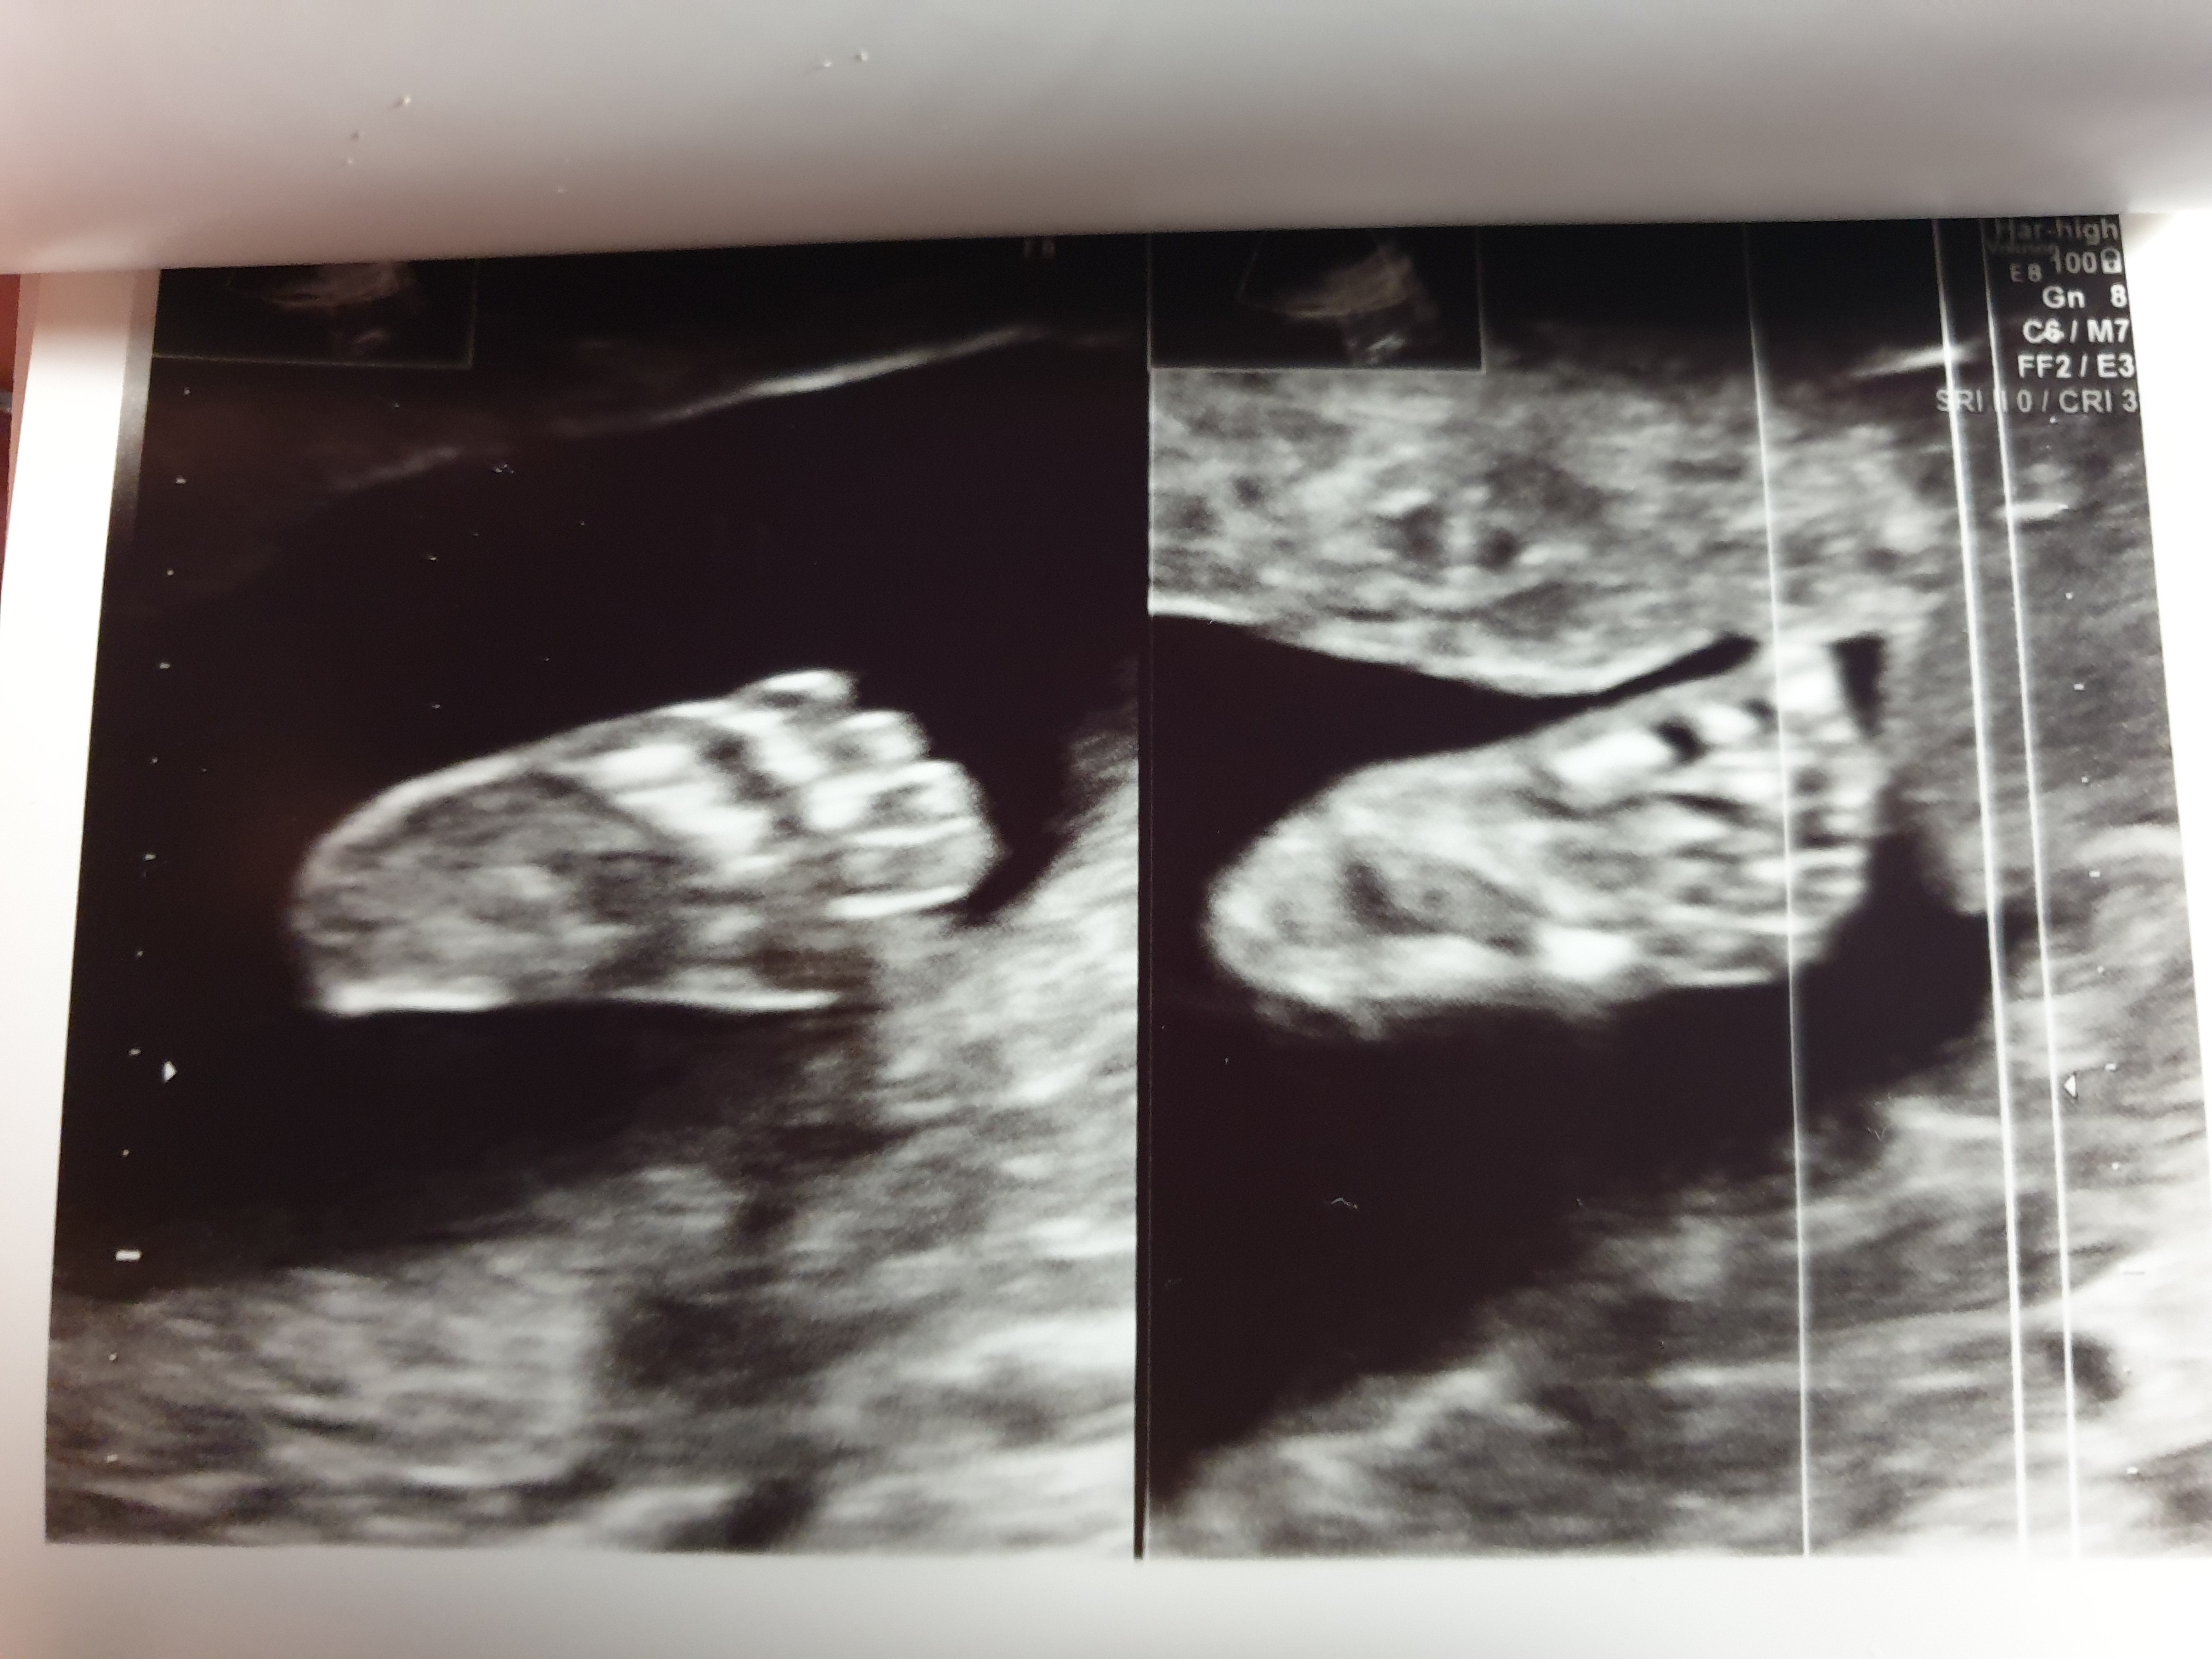

Rośnie uparte stworzenie, nie chciał się mały pokazać i skakałam w gabinecie przez 40 min, spacer i jeszcze raz USG ale udało się wszystko sprawdzić :)

Waży całe 420g więc jest dosyć duży, ale ja mam 178 cm wzrostu, sama urodzilam się jako klocek więc to nic dziwnego :)